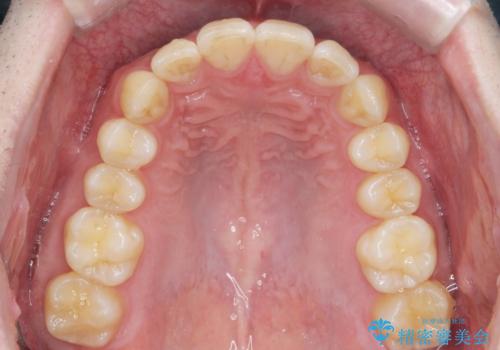

前歯のがたつきをなおしたい マウスピース矯正

- 気になる前歯のがたつきをきれいにしたい。と矯正治療を希望され来院されました。

大きな歯列の乱れはないため、倒れ込んでいる奥歯の傾きの改善、前歯のがたつきを改善する治療を計画します。

見た目が良くなっただけではなく、歯ブラシがしやすくなった!と治療後の歯並びに喜んでいただくことができました。